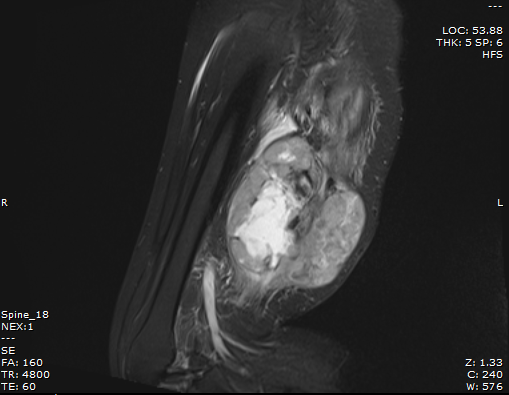

Kết quả chụp cộng hưởng từ (MRI) tại Bệnh viện Bãi Cháy xác định trong cơ vùng đùi phải có khối kích thước lớn 12,5x9,7cm, xâm lấm thần kinh hông to đoạn 1/3 dưới đùi phải. Các bác sĩ đã hội chẩn chuyên khoa ung bướu và chấn thương chỉnh hình, quyết định phẫu thuật lấy bỏ khối sarcoma.

Hình ảnh khối sarcoma sụn ác tính của bệnh nhân trên phim chụp cộng hưởng từ (MRI)